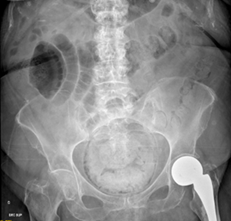

Radiografía de abdomen: Hallazgos sugestivos de cistitis enfisematosa con gas rodeando el perímetro vesical; fecaloma rectal. Asas enterales discretamente distendidas en relación con íleo paralítico secundario en flanco derecho. Portadora de prótesis parcial de la cadera izquierda (Figura 1).

Se visualiza radiolucencia en téorica pared vesical compatible con gas, que se encuentra ampliamente repleccionada y un gran fecaloma.

Figura 1 Radiografía simple de abdomen